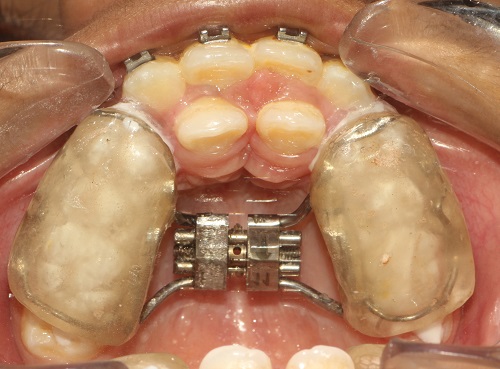

The various treatment offered in the department includes fixed orthodontic treatment with metal, ceramic,self-ligating brackets, treatment with mini-implants, Rapid Maxillary Expansion appliances, orthognathic surgeries to correct facial deformities, distraction osteogenesis procedures with Internal and External distractors, treatment of cleft lip and palate, Pre-surgical Naso Alveolar Moulding on cleft cases, Fixed functional treatment with Forsus, Powerscope, Herbst etc, Lingual Orthodontic treatment, Myofunctional Appliance Therapy, Aligner Orthodontic Treatment ,Myofunctional trainers, Splints- For Temporomandibular joint disorders as well as Class III correctors in growing individuals with appliances such as Tandem Traction Bow Appliance.